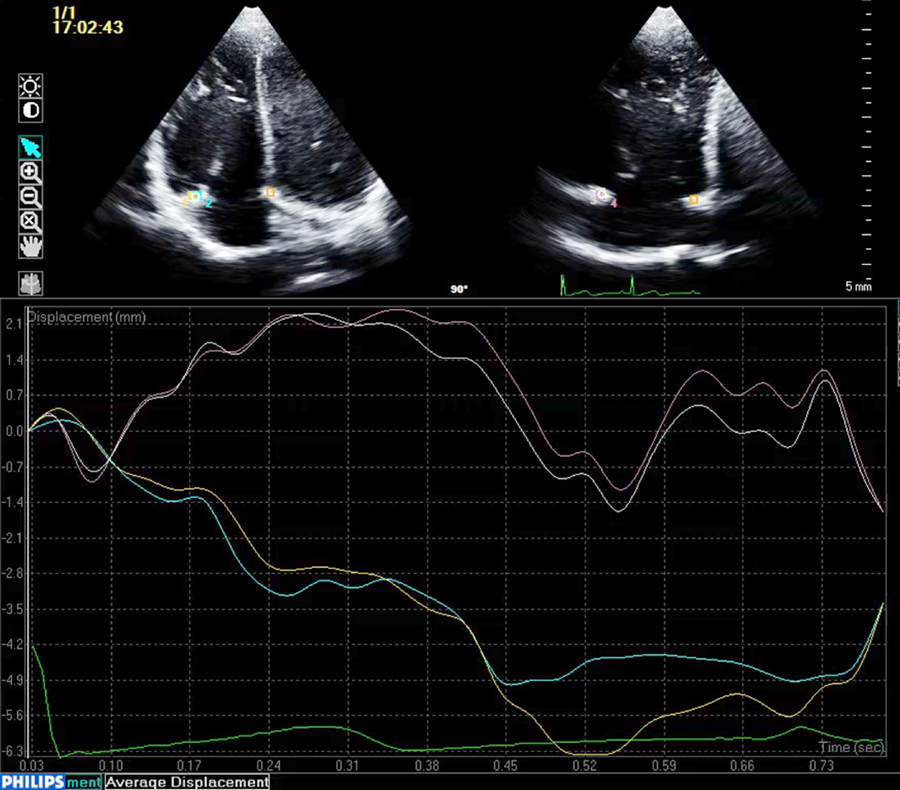

左心低形成症候群と右側心房相同における房室弁輪面積時相変化:弁輪スペックルトラッキングを用いた検討Annular Atrioventricular Valve Area Dynamics in Patients with Hypoplastic Left Heart Syndrome and Right Atrial Isomerism: Insights Using Speckle-Tracking of the Atrioventricular Valve Annulus